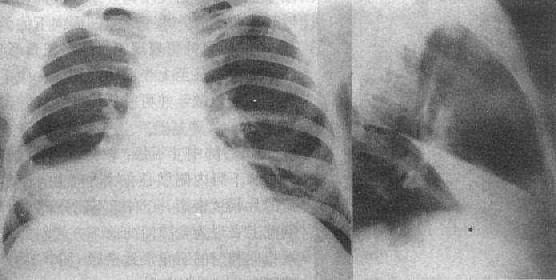

(1)一侧性肺不张:X线现为患侧肺野均匀致密,纵隔向患侧移位,肋间隙变窄(图3-1-7)。健侧肺可有代偿性肺气肿。

图3-1-7 一侧性肺不张

左侧支气管阻塞引起左侧全肺不张,显示左侧肺野均匀致密,

纵隔向患侧移位,肋间隙变窄,膈升高